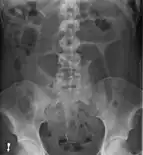

- Abdominal x-ray – tire-like shadow arising from right iliac fossa and passing to left

Coffee bean sign in a person with sigmoid volvulus